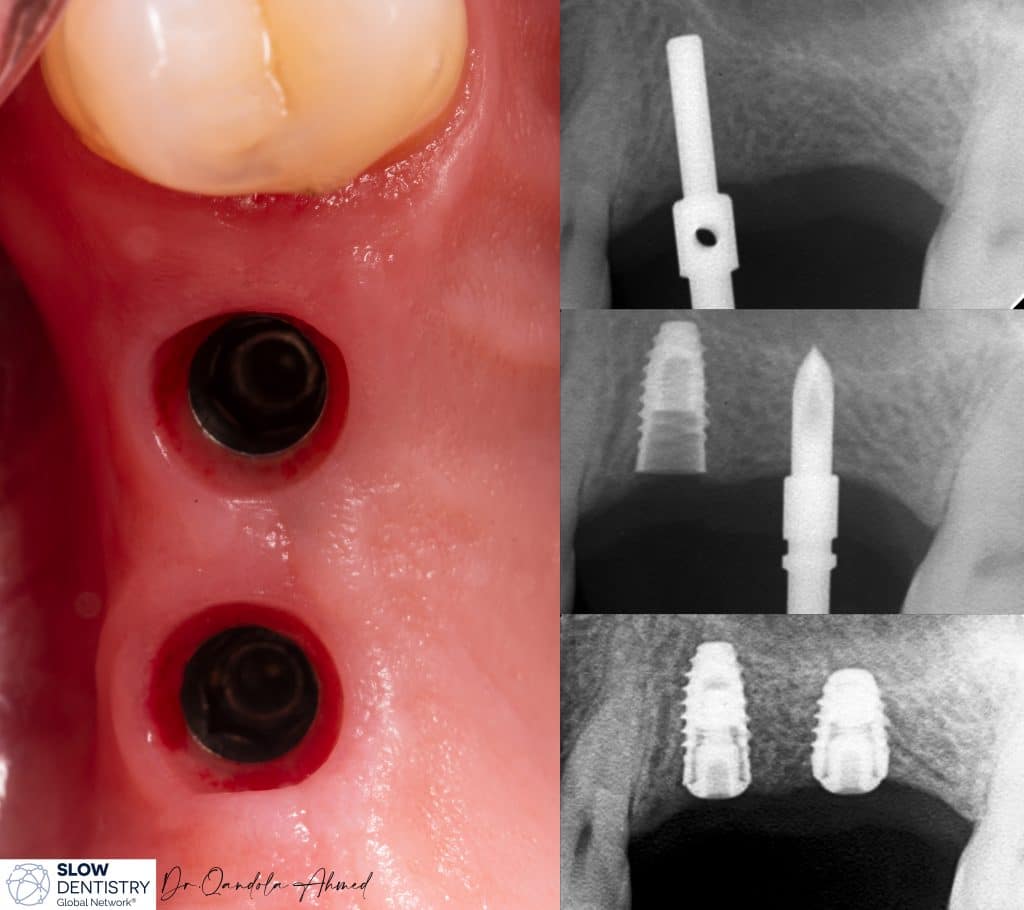

Months After Implants placement , Short Implants Used To Avoid Any Extra Surgery (Sinus Lift etc. )